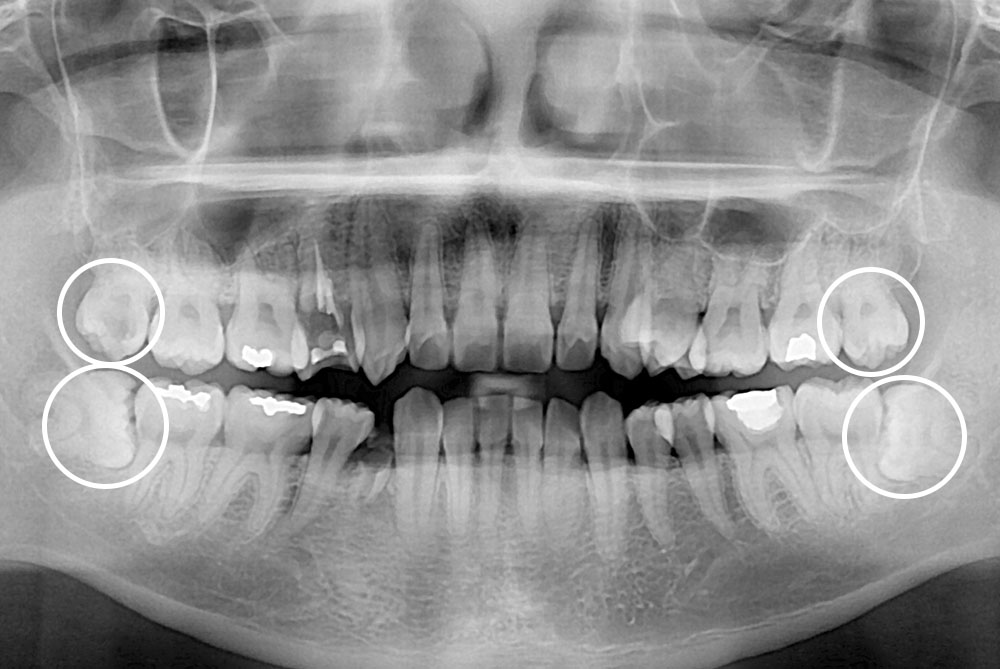

[사랑니] 매복 사랑니 발치

치료후 : 2022-07-16

세종치과는 구강악안면외과학 박사이신 원장님이 발치하는 치과입니다.